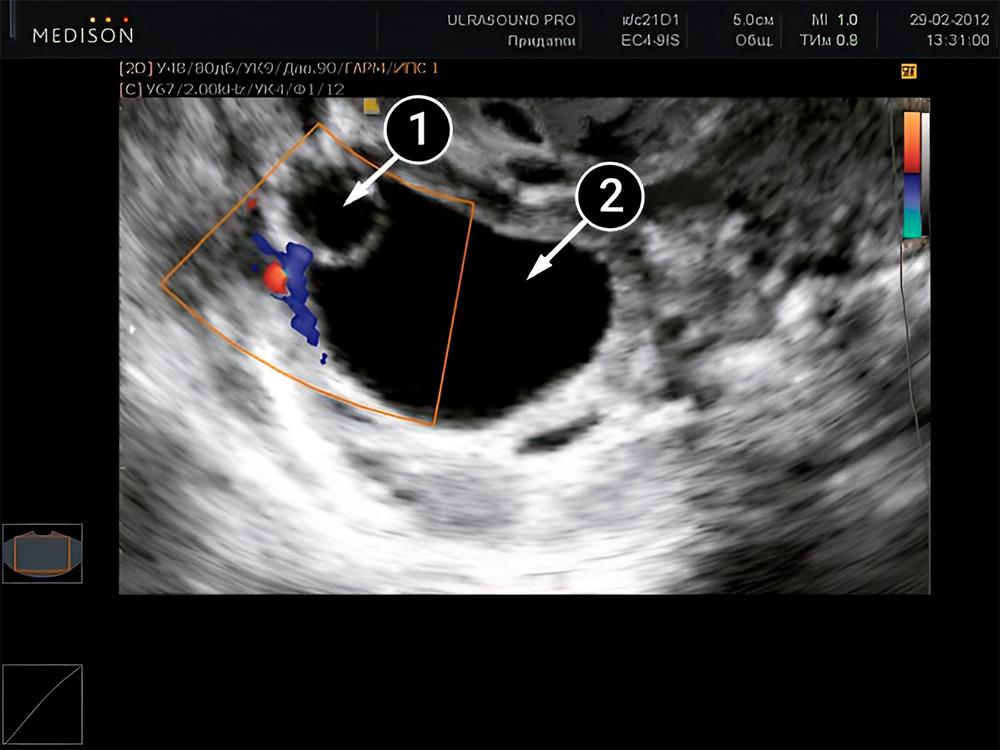

La segunda imagen muestra los ovarios. La cavidad oscura redondeada es el folículo dominante. Por lo general, con cada ciclo menstrual, hay un solo folículo que está por delante de los demás en términos de crecimiento. Al abrirse, libera un óvulo que está listo para ser fertilizado. Pero en algunos casos, puede haber dos o incluso tres folículos dominantes. Esto hace que la posibilidad de tener un embarazo múltiple sea mucho mayor. Una hora después de su ruptura, el óvulo ingresa a la cavidad abdominal y de ahí pasa a las trompas de Falopio por medio de la Fimbria, donde se encontrará con los espermatozoides; de allí se desplaza, gracias a las contracciones musculares, hasta el útero.